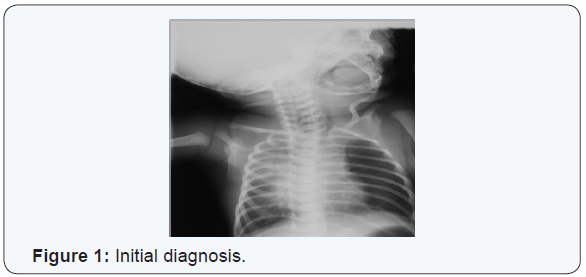

An initial diagnosis was made of aspiration pneumonitis (Figure 1). After an initial turbulent period the baby’s clinical condition improved. On the fourth day of life repeated attempts to pass a nasogastric tube for feeding failed. Intraoesophageal suction continued to yield copious aspirates. A tube containing light barium was passed and a plain radiograph of the neck and chest taken (Figure 2). This demonstrated a blind proximal oesophageal pouch. A plain abdominal radiograph showed abundant gastric and intestinal gas (Figure 3). Bronchoscopy subsequently confirmed oesophageal Atresia. Clinical evaluation and an echocardiogram excluded congenital heart disease. The baby underwent primary surgical repair on the eighth day of life and has since recovered.